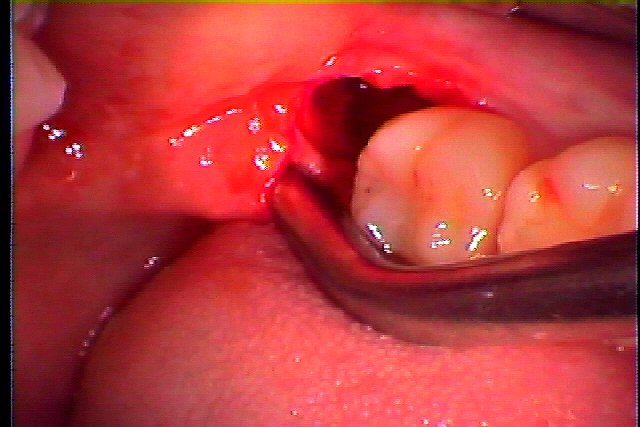

左下の親知らずの抜歯 完全埋伏歯の抜歯|お知らせ |広島市安佐南区の歯科医院 左下の親知らずの抜歯 完全埋伏歯の抜歯 トップ お知らせ・ブログ お知らせ 左下の親知らずの抜歯 完全埋伏歯の抜歯 左下の親知らずの抜歯 完全埋伏歯の抜歯 ここに親知らずが埋伏しています 今もですが腫れて痛むとのこと このように横に向かって生えているようです 全体像がわかるようにパノラマを取りました 切開を加えていきます 歯冠部を分割して抜歯を行っています 縫合して終了となります このようにきれいに取れました 1週間後に抜糸を行っていきます Web診療予約 初めての方へ 選ばれ続ける理由 院内設備について 歯が痛いしみる一般歯科 歯がぐらぐらする歯周病 健康な歯を保ちたい予防歯科 子供の虫歯予防をしたい小児歯科 銀歯をセラミックに審美歯科 白い歯を目指しませんか?ホワイトニング 矯正専門医がいるので安心矯正歯科 抜けた歯を補いたいインプラント・入れ歯 医院案内 スタッフ紹介 メリィハウス歯科クリニックオフィシャルホームページ ラベンダー歯科クリニックオフィシャルホームページ お知らせ・ブログ ホーム 診療科目 一般歯科 歯周病治療 予防治療 小児歯科 審美治療 ホワイトニング 矯正歯科 入れ歯・インプラント マウスピース矯正 初めての方へ 院長・スタッフ 設備紹介 医院案内・アクセス メニューを閉じる